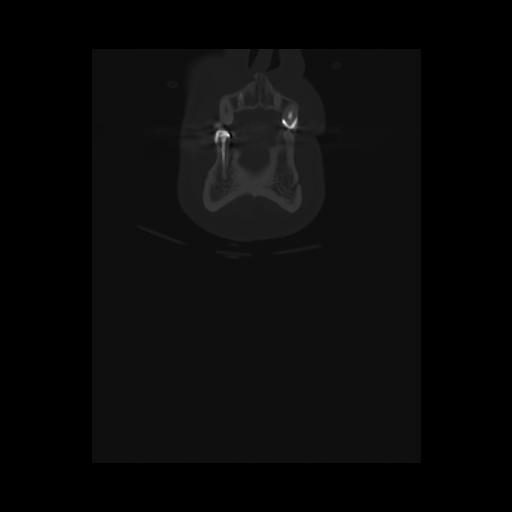

16 HUESO,,Coronal,2.000,HUESO,Coronal,